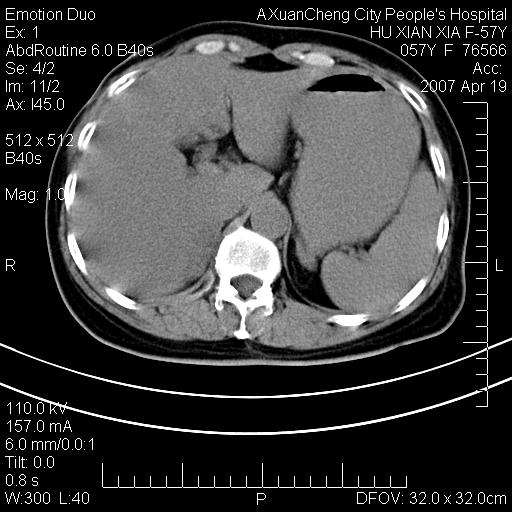

标题: CT7778:[原创]F,57Y腹痛待查,胸片提示肺部占位,应当很典型 [打印本页]

标题: CT7778:[原创]F,57Y腹痛待查,胸片提示肺部占位,应当很典型

胸片提示肺部占位

双侧肾上腺增大,有分叶,密度均匀,考虑转移建议查原发灶

1.双侧肾上腺占位,转移首先考虑。

双侧肾上腺结节样肿块,结合肺部肿块,考虑肺癌肾上腺转移。

双侧肾上腺及腹膜后淋巴结增大,结合胸片提示肺部占位,考虑肺癌双侧肾上腺及腹膜后淋巴结转移.